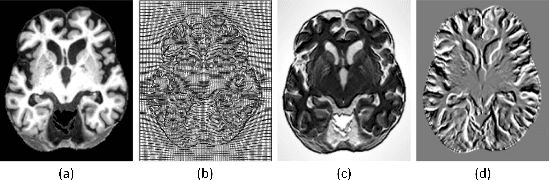

Abstract:Accurate registration of medical images is vital for doctor's diagnosis and quantitative analysis. In this paper, we propose a new deformable medical image registration method based on average geometric transformations and VoxelMorph CNN architecture. We compute the differential geometric information including Jacobian determinant(JD) and the curl vector(CV) of diffeomorphic registration field and use them as multi-channel of VoxelMorph CNN for second train. In addition, we use the average transformation to construct a standard brain MRI atlas which can be used as fixed image. We verify our method on two datasets including ADNI dataset and MRBrainS18 Challenge dataset, and obtain excellent improvement on MR image registration with average Dice scores and non-negative Jacobian locations compared with MIT's original method. The experimental results show the method can achieve better performance in brain MRI diagnosis.

Abstract:Accurate segmentation of brain tissue in magnetic resonance images (MRI) is a difficult task due to different types of brain abnormalities. In this paper, we review the deformation method focus on the construction of diffeomorphisms, address clearly a new formation of the deformation problem for moving domains, and we apply it in natural images, face images and MRI brain images. And we use a new method to construct diffeomorphisms through a completely different approach. The idea is to control directly the Jacobian determinant and the curl vector of a transformation and use them as one CNN channel with other modalities(T1-weighted, T1-IR and T2-FLAIR) to get more accurate results of brain segmentation. More importantly, we discuss the influence of some optimization parameters to precision analysis of MRI brain segmentation by both numerical experiments and theoretical analysis. We test this method on the IBSR dataset and MRBrainS18 dataset based on VoxResNet and prove the influence of three parameters on the accuracy of MRI brain segmentation.Finally, we also compare the segmentation performance of our method in two networks, VoxResNet and 3D U-Net network. We believe the proposed method can advance the performance in brain segmentation and clinical diagnosis.

Abstract:Accurate segmentation of brain tissue in magnetic resonance images (MRI) is a diffcult task due to different types of brain abnormalities. Using information and features from multimodal MRI including T1, T1-weighted inversion recovery (T1-IR) and T2-FLAIR and differential geometric features including the Jacobian determinant(JD) and the curl vector(CV) derived from T1 modality can result in a more accurate analysis of brain images. In this paper, we use the differential geometric information including JD and CV as image characteristics to measure the differences between different MRI images, which represent local size changes and local rotations of the brain image, and we can use them as one CNN channel with other three modalities (T1-weighted, T1-IR and T2-FLAIR) to get more accurate results of brain segmentation. We test this method on two datasets including IBSR dataset and MRBrainS datasets based on the deep voxelwise residual network, namely VoxResNet, and obtain excellent improvement over single modality or three modalities and increases average DSC(Cerebrospinal Fluid (CSF), Gray Matter (GM) and White Matter (WM)) by about 1.5% on the well-known MRBrainS18 dataset and about 2.5% on the IBSR dataset. Moreover, we discuss that one modality combined with its JD or CV information can replace the segmentation effect of three modalities, which can provide medical conveniences for doctor to diagnose because only to extract T1-modality MRI image of patients. Finally, we also compare the segmentation performance of our method in two networks, VoxResNet and U-Net network. The results show VoxResNet has a better performance than U-Net network with our method in brain MRI segmentation. We believe the proposed method can advance the performance in brain segmentation and clinical diagnosis.